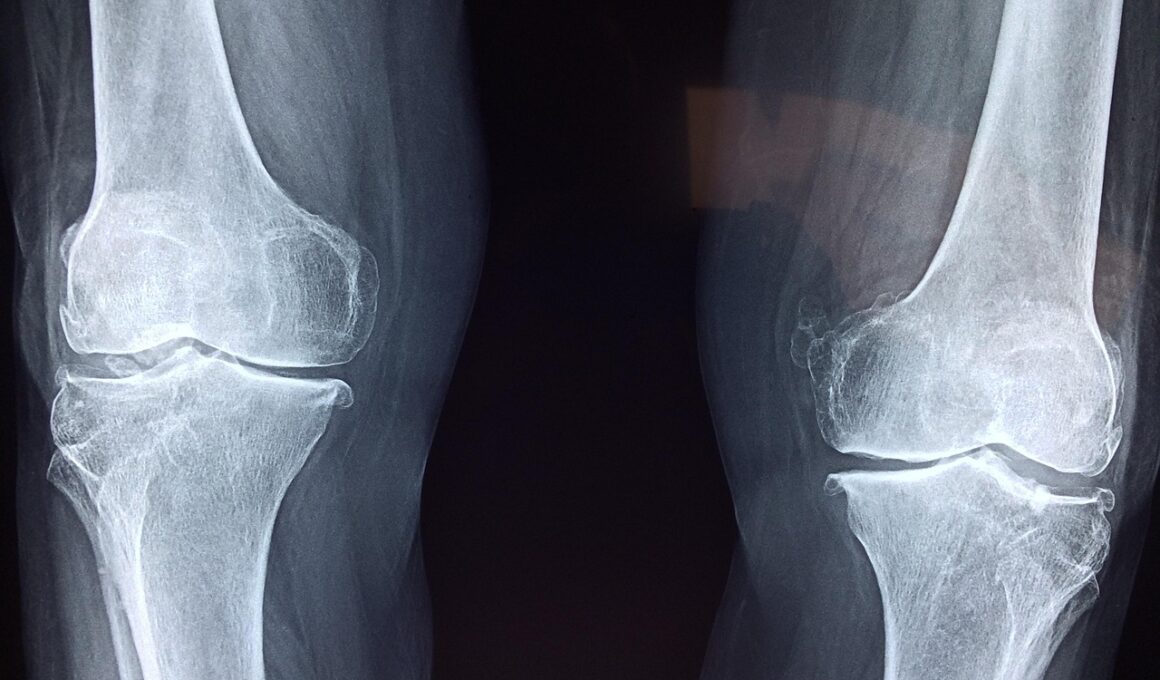

Sports medicine has witnessed significant advancements in recent times, particularly in the realm of cartilage repair surgeries. These innovations are crucial for athletes who suffer from cartilage injuries, as these injuries can severely restrict their performance and quality of life. Various surgical techniques have been devised to aid in the regeneration of damaged cartilage, helping athletes return to their sports quickly and effectively. Options such as microfracture, autologous chondrocyte implantation, and osteochondral autografts provide tailored solutions for different injury types. Moreover, researchers are exploring the use of biomaterials and scaffolding techniques to create an artificial environment for cartilage healing. The efficacy of these modern procedures is being assessed through various clinical trials, further contributing to the evolving landscape of sports medicine surgery. Each method varies in its approach and effectiveness, so understanding these options is essential for athletes seeking to make informed decisions regarding their treatment. Continuous research aims to improve these techniques, ensuring they offer the best possible outcomes for patients. This surge of innovation is positively impacting not only recovery times but also the long-term health of athletes’ joints.

Current techniques in cartilage repair emphasize minimally invasive surgical methods that reduce recovery periods while enhancing healing outcomes. One of the most notable advancements is the development of arthroscopic procedures, which allow surgeons to operate through small incisions. This technique minimizes tissue damage and leads to shorter rehabilitation periods for patients. Additionally, procedures like microfracture enable the creation of small holes in the bone to promote cartilage healing. This technique is popular due to its relative simplicity and effectiveness. Autologous chondrocyte implantation is another major breakthrough wherein a patient’s own cartilage cells are harvested, cultured, and then re-implanted back into the damaged area. This innovative method has shown promising results in regenerating cartilage with a more natural composition. Furthermore, advancements in synthetic biomaterials have also provided surgeons with tools to support chondral repair, offering further options for patients with severe cartilage deterioration. Technologies continue to evolve, and combined approaches, integrating cell therapy with scaffold technology, show promise in developing tissue-engineered solutions. As these techniques are refined, they contribute to enhanced functional outcomes for athletes following surgery.